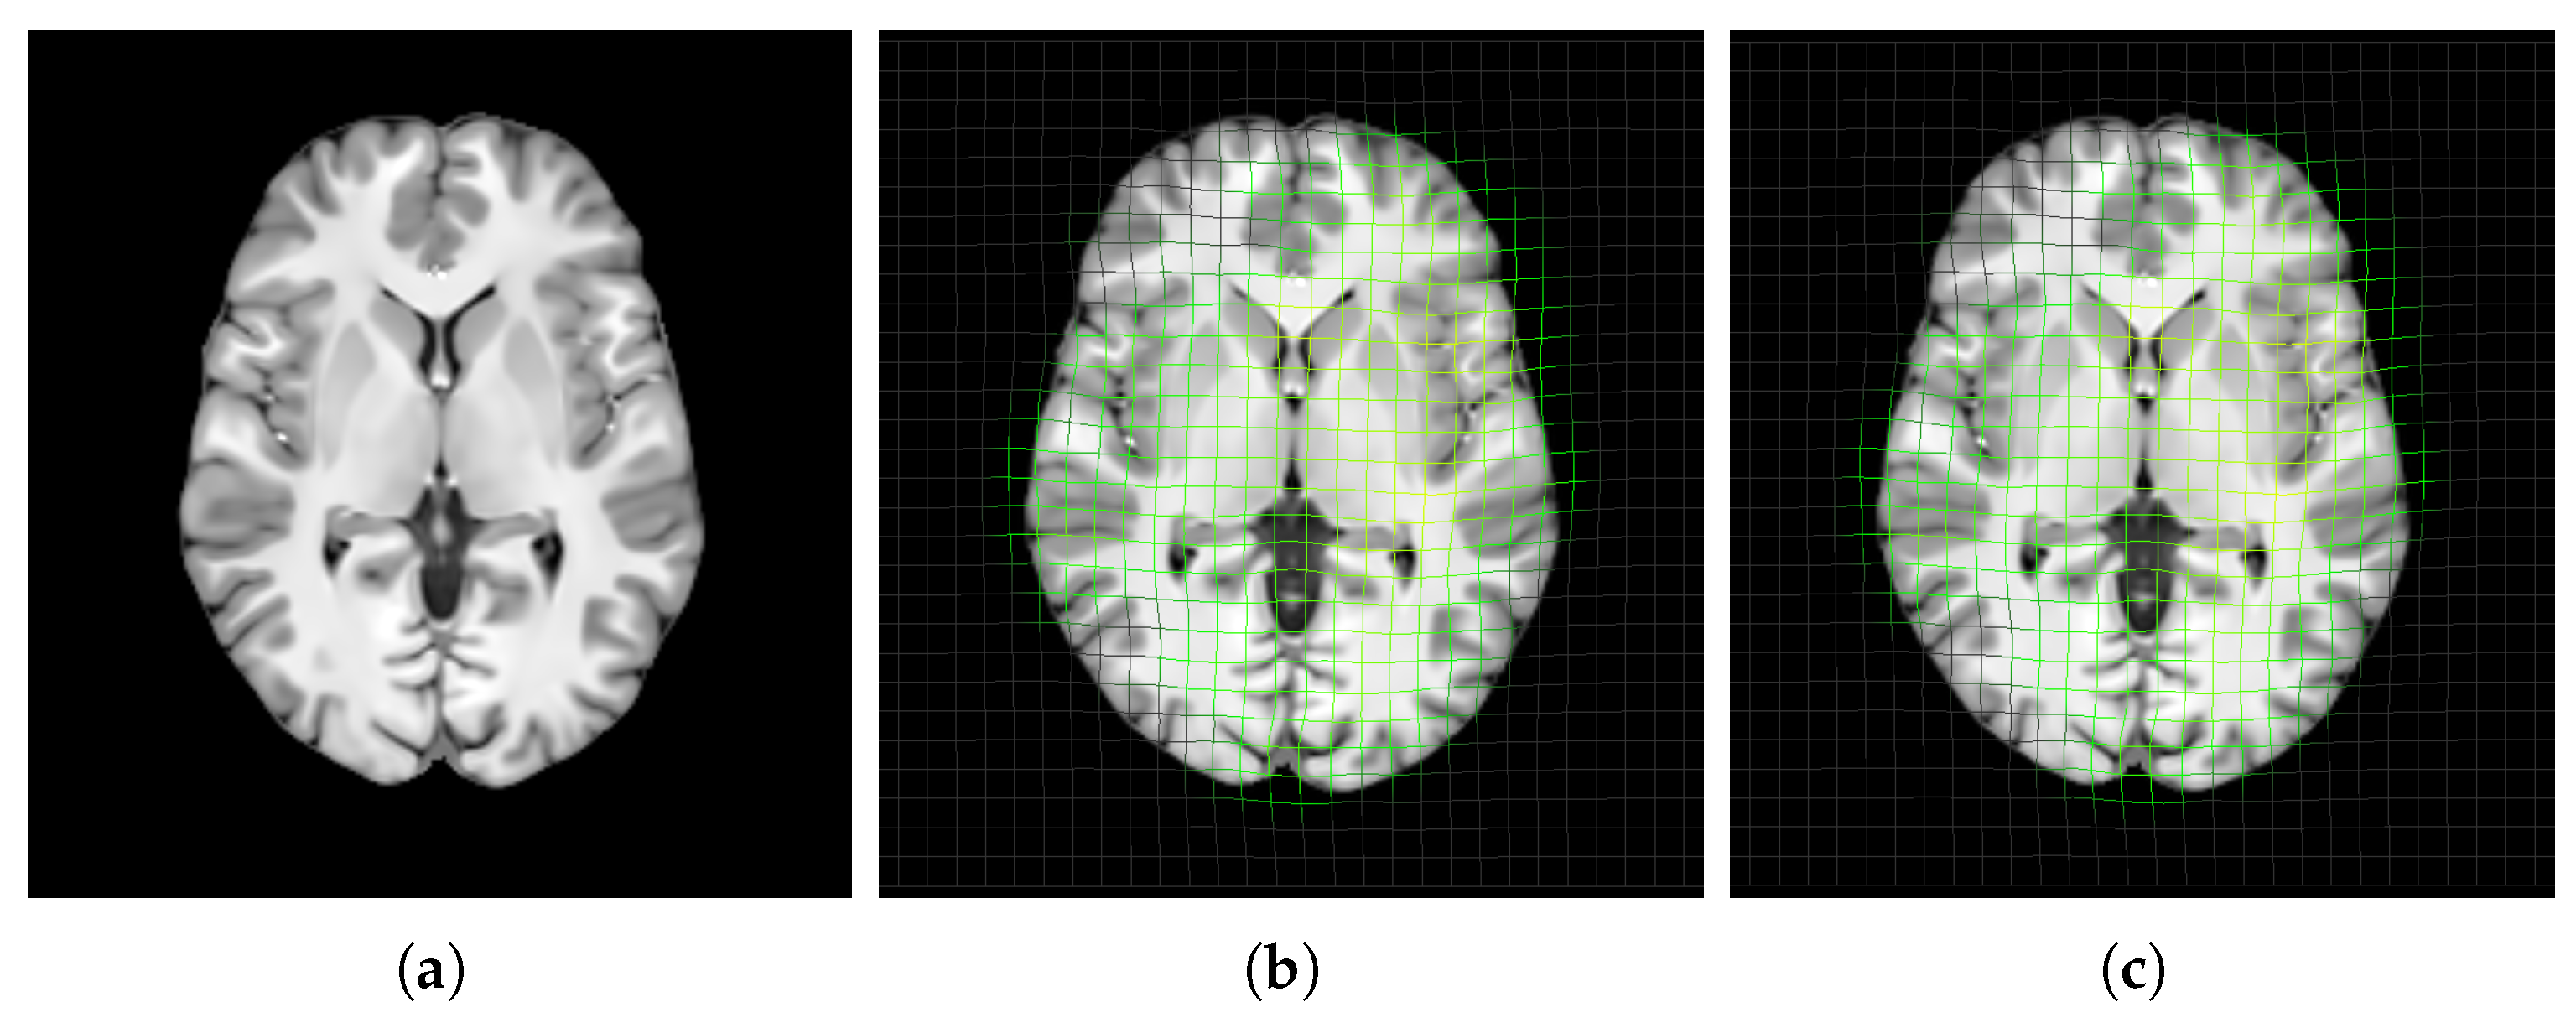

3.4.1. Unbiasedness of Template Structure

4.1. Unbiasedness of Template Structure